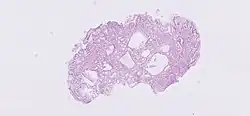

H&E stain of fundic gland polyp showing shortening of the gastric pits with cystic dilatation

The development of polyps depends on the underlying disorder.[17] In sporadic cases of FGPs, more than 90% of patients have activating mutations in the β-catenin gene, so that they may be considered "neoplastic" polyps.[18]